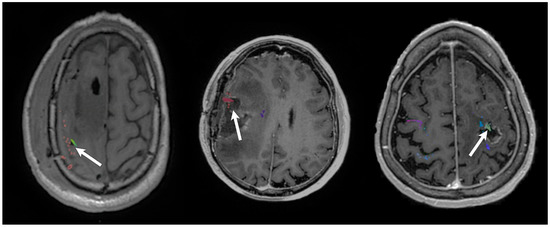

2.1. Transcranial Magnetic Stimulation

2.2. Diffusion Tensor Imaging

2.3. Perioperative Overlays